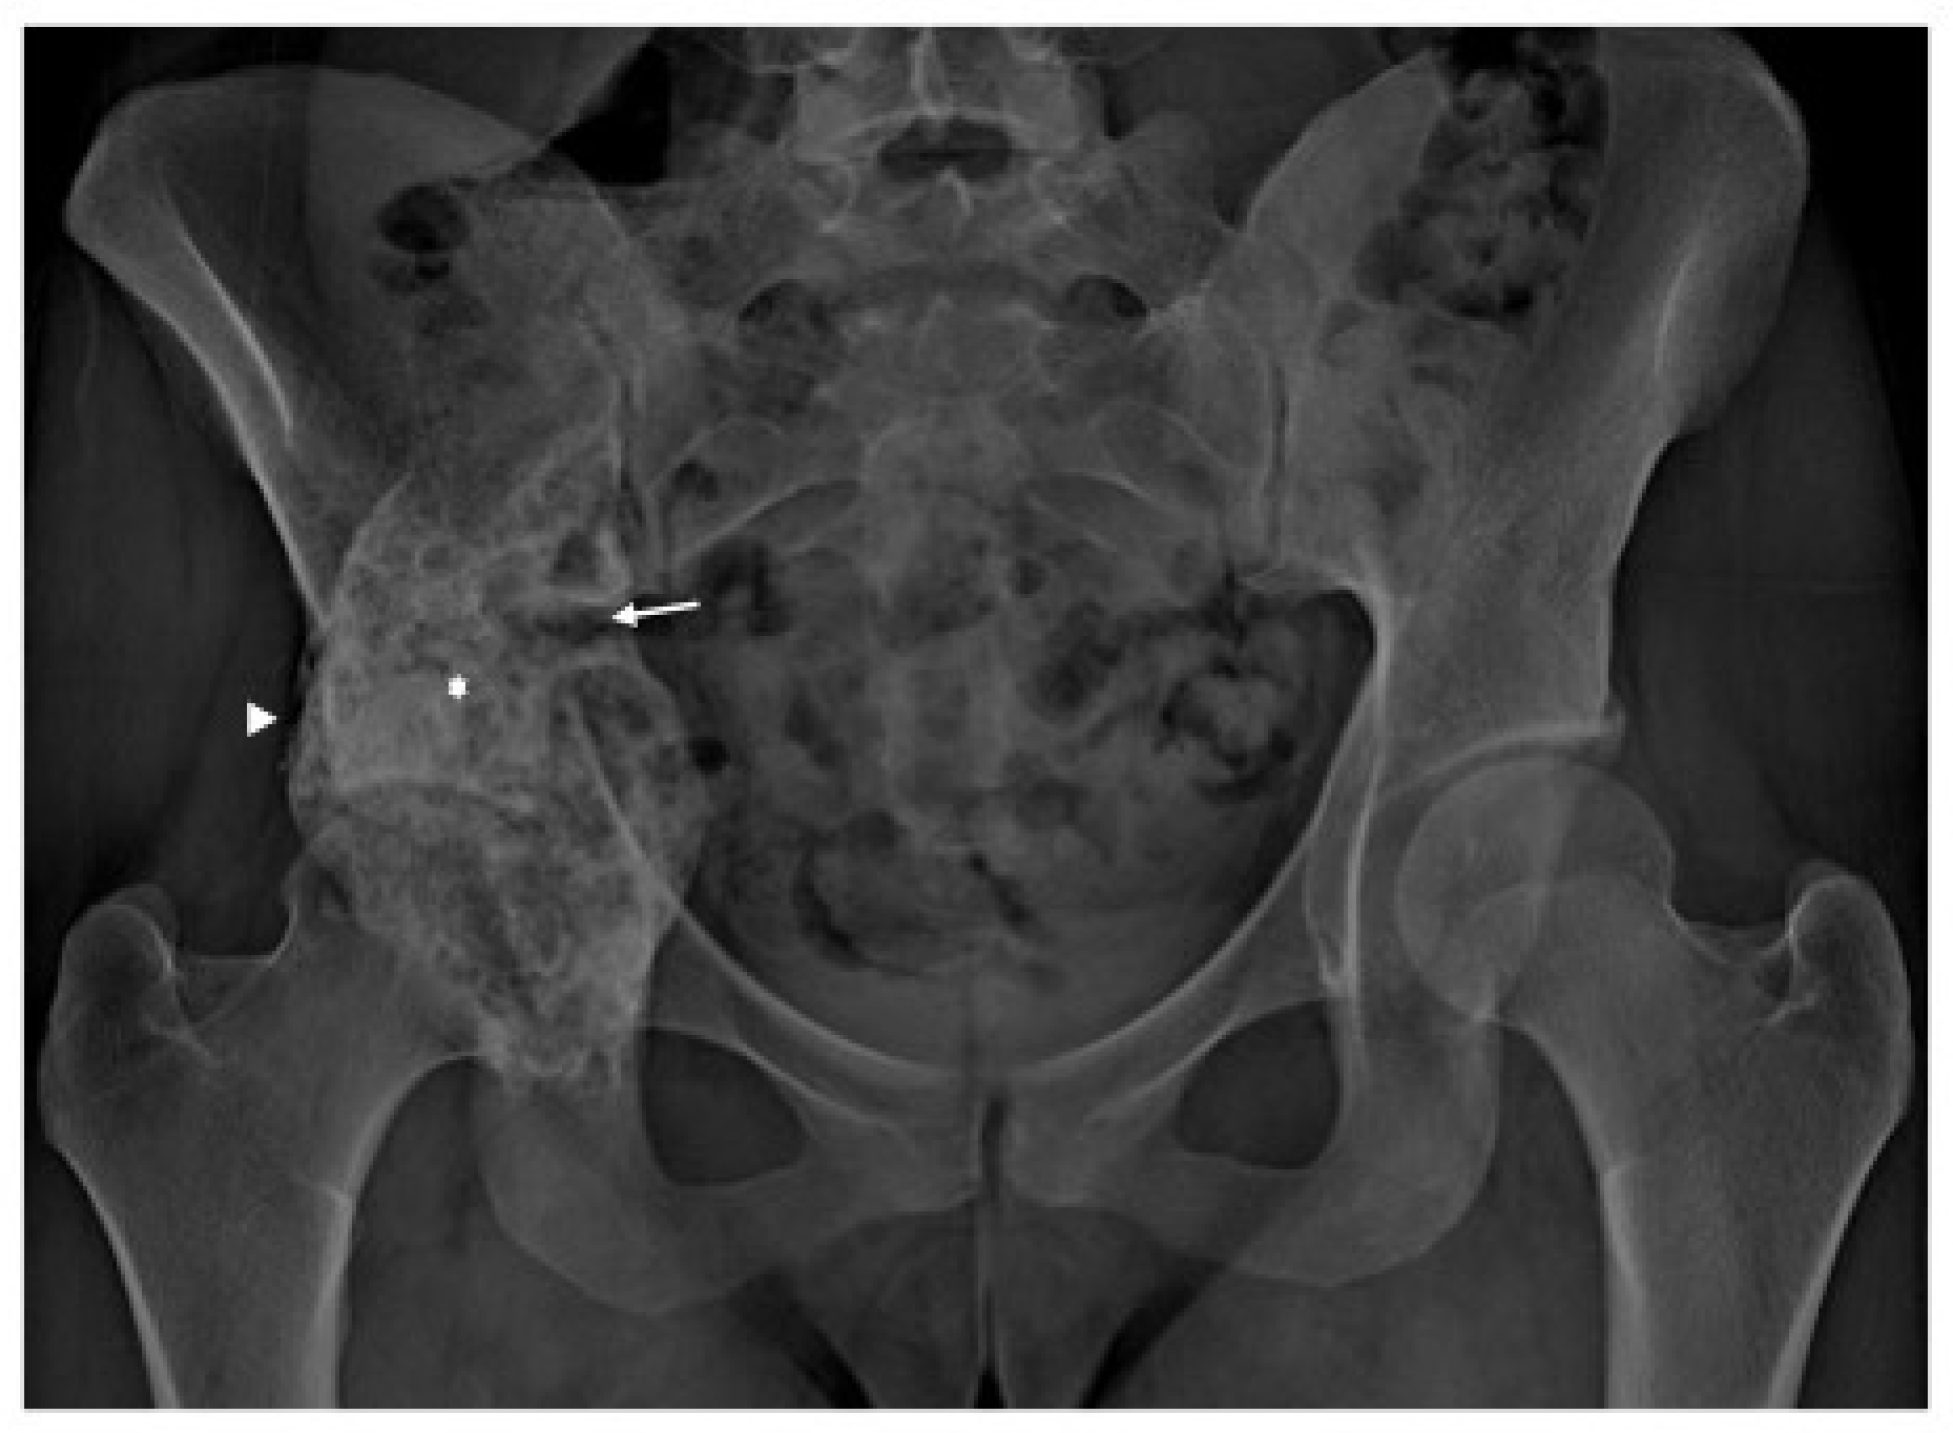

2. Case Presentation